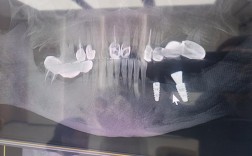

- 拍X光片:评估牙槽骨状况(是否有骨吸收),检查种植体位置、基台和牙冠的密合度。

- 根据检查结果,医生会做出诊断,确定是正常愈合还是存在问题,以及问题的性质和严重程度。